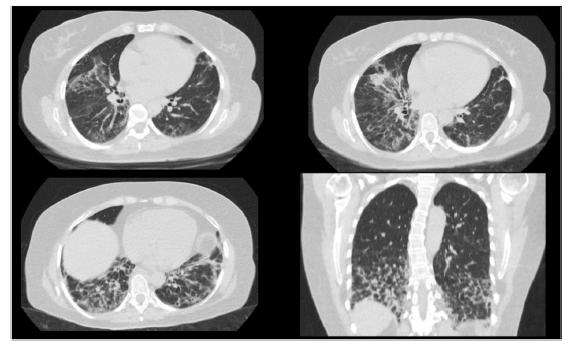

A 50-year-old female patient, consultation due to a medical condition of 2 months of evolution consisting of intermittent episodes of dry cough, associated with dyspnea and deterioration of its functional class, MMRC 4, she does not report fever, subjective weight loss, for which she is directed from external consultation to the emergency service. Within her antecedents she does not mention chronic pathologies, no smoking or biomass exposure, highlights hysterectomy plus pomeroy for uterine myomatosis. She enters the emergency service in regular general conditions, broken speech, blood pressure (Pa): 115/70 mmHg, heart rate (h) 80 beats per minute (bpm), breathing frequency (fr) 22 breaths per minute (rpm), oxygen saturation 89-90% with ambient oxygen, the lung auscultation reveals the presence of velcro crepitus in both lung bases, paraclinical tests that show normal leukocytes, no anemia, PCR 1.67, preserved kidney function. A high-resolution chest tomography was performed (TACAR) (Fig. 1) where consolidative images were described predominantly in the lung bases, presence of air bronchogram, associated with subpleural nodules, it is initially considered a manifestation of community-acquired pneumonia, the presence of risk for Gram positive germs is also considered under the suspicion of septic seeding. Despite the antibiotic treatment, no improvement was observed in his clinical condition. It is considered that in the onset of his condition there is no presence of symptoms suggestive of an ongoing infectious process, and because it is a chronic dyspnea associated with tomographic findings, the possibility of organizing pneumonia is raised, she was taken to bronchoscopy plus biopsy, as well as percutaneous biopsy. In order to clarify the etiology of her condition, she was questioned about drug use, radiation exposure, malignancy and paraclinical tests with an autoimmunity profile were complemented (Table 1), which is normal. A percutaneous lung biopsy report was obtained with a histological pattern consistent with organizing pneumonia (Fig. 3). Management is started with methylprednisolone in boluses of 500 mg iv day for 3 days, then she switched to oral corticosteroid, with which an improvement in her dyspnea and radiological improvement was observed (Fig. 2), she is discharged with corticosteroid and home oxygen management. During outpatient follow-up, pulmonary function test is performed: CVF: 60%, DLCO: 15%. The patient abandoned the treatment by her own decision, presenting worsening of her dyspnea and appearance of joint pain and Raynaud's phenomenon. Autoimmunity profile is performed again, this time the report is positive for Anti Jo and Anti RO, the patient is considered to meet Solomon criteria for which antisynthetase syndrome is diagnosed. Faced with a new episode of relapse, she is hospitalized and a cycle of intravenous cyclophosphamide is started, with which she has presented improvement in her disease pattern.

Characteristic radiographic findings within organizational pneumonia consist of ground glass opacities (88%), consolidation (83%), peribronchovascular opacities (52%), reticular infiltrates (38%) bronchiectasis (33%), interstitial nodules (27%), reverse halo sign (17%). Being the compromise predominantly in the lower lobes and subpleural distribution.7,8 One of the important characteristics regarding radiological evolution is that the findings have a changing pattern over time. As can be seen in Figs. 1 and 2, a pattern of pulmonary consolidation is presented with greater involvement of the pulmonary bases, with presence of subpleural nodules and small areas of ground glass.